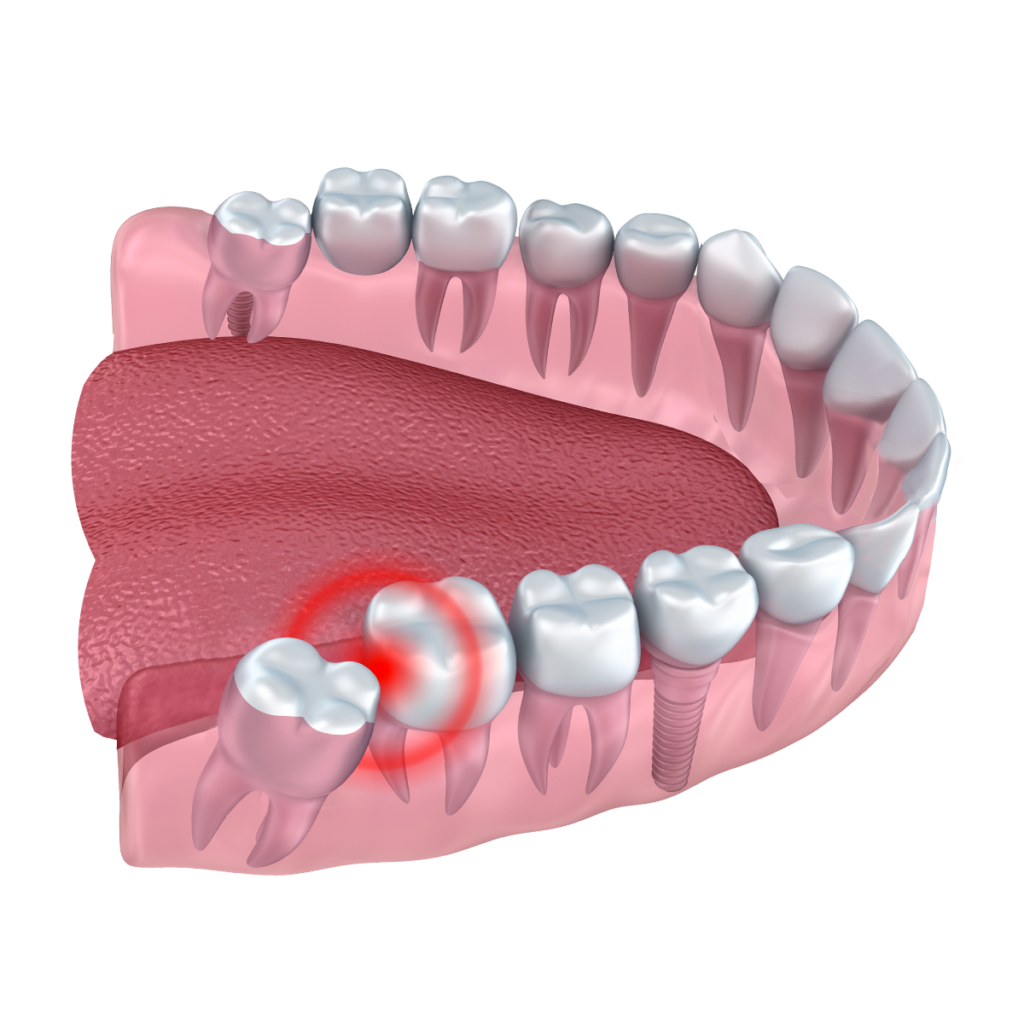

- Wisdom tooth removal,

- Dental implant,